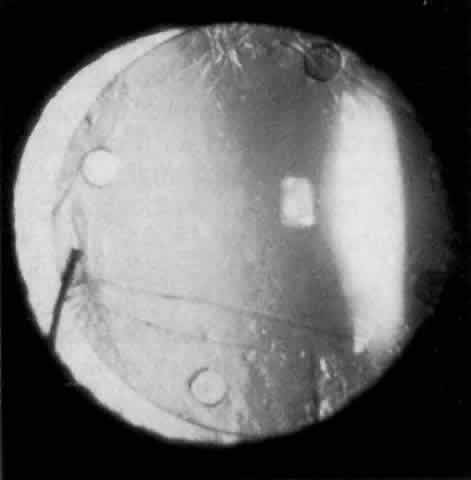

Cortical lens fragments retained in either the anterior chamber or the vitreous can also obstruct the trabecular meshwork in the form of free lens particles or macrophages swollen with lens material (Figs. 2 and 3). Glaucoma does not occur in all eyes that contain cortical remnants; the inflammatory response may be more pronounced and prolonged in eyes containing a higher amount of lens material. When inflammation is marked, keratic precipitates and sometimes a hypopyon may be present. Distinction between this sterile inflammatory endophthalmitis and infectious endophthalmitis can be difficult and may depend on the initial response to therapy. The presence or absence of IOP elevation is not helpful in making this distinction because IOP may be normal or elevated in both situations.